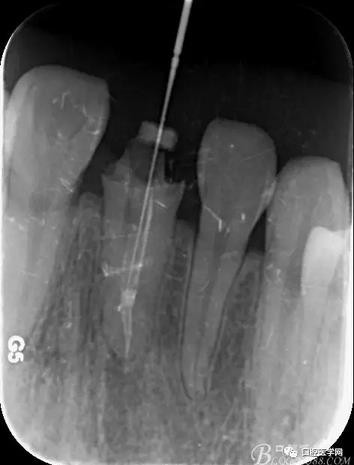

輔助檢查:X線見根尖區(qū)輕低密度影像,根尖1/3見根充物密實(shí)恰填,根管上2/3見折斷纖維樁,與根管密實(shí)。

術(shù)前X線片